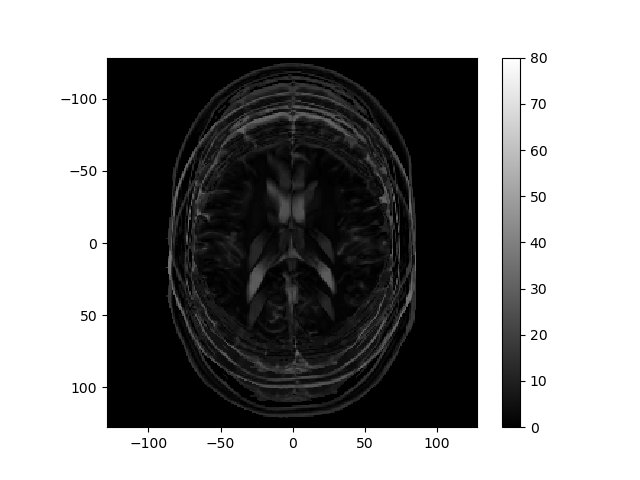

Consider how the image would change if the k-space data were multiplied by \sin^2(\cdot) or \cos^2(\cdot) of k_r or k_c. Below are several k-space representations that have been distorted in this way. In each case, assume that only the magnitude of the k-space data is changed. Match each k-space image with the corresponding reconstructed image, and enter your results from the corresponding pull-down list.

matching reconstructed image: